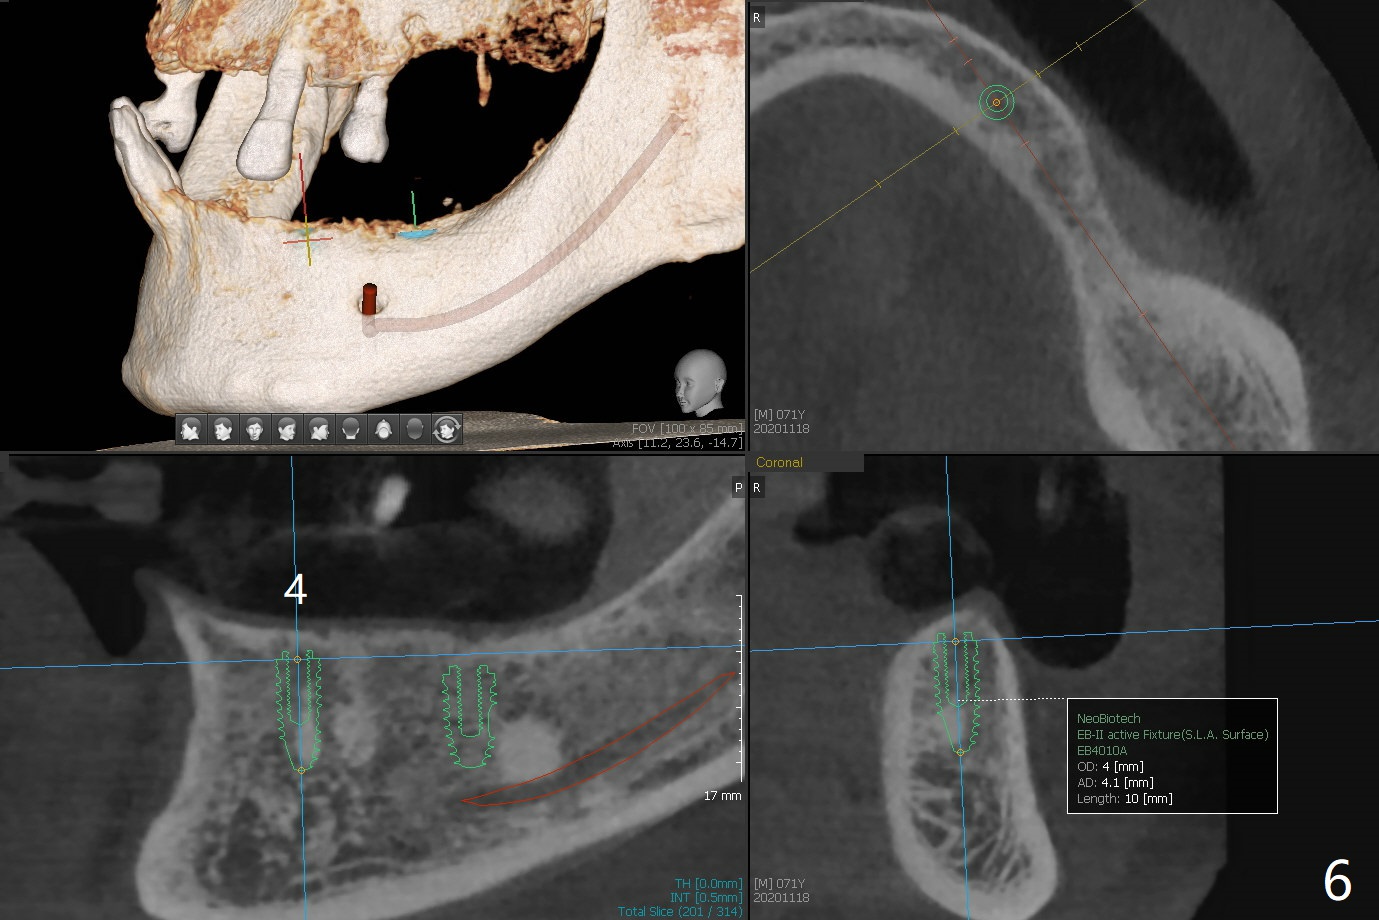

71岁男主诉下颌局部托牙松动(图一),侧切牙不适,临床检查显示后者有咬合创伤,局部卫生不佳,对策:洗牙以及左下4,6植入植体,放置带有球的基台(图五,六)。上颌局部托牙有三个自然牙,挺稳定,但是颈部缺损严重,需要修补(图二,三),左上5远中龋齿需要根管治疗(图四),尽量延长基牙寿命。一个月后病人回来却要求处理松动疼痛右下2,不愿意种植,与3固定和调整咬合,症状消失。Return to No Caries Overdentures Xin Wei, DDS, PhD, MS 1st edition 11/18/2020, last revision 12/13/2020